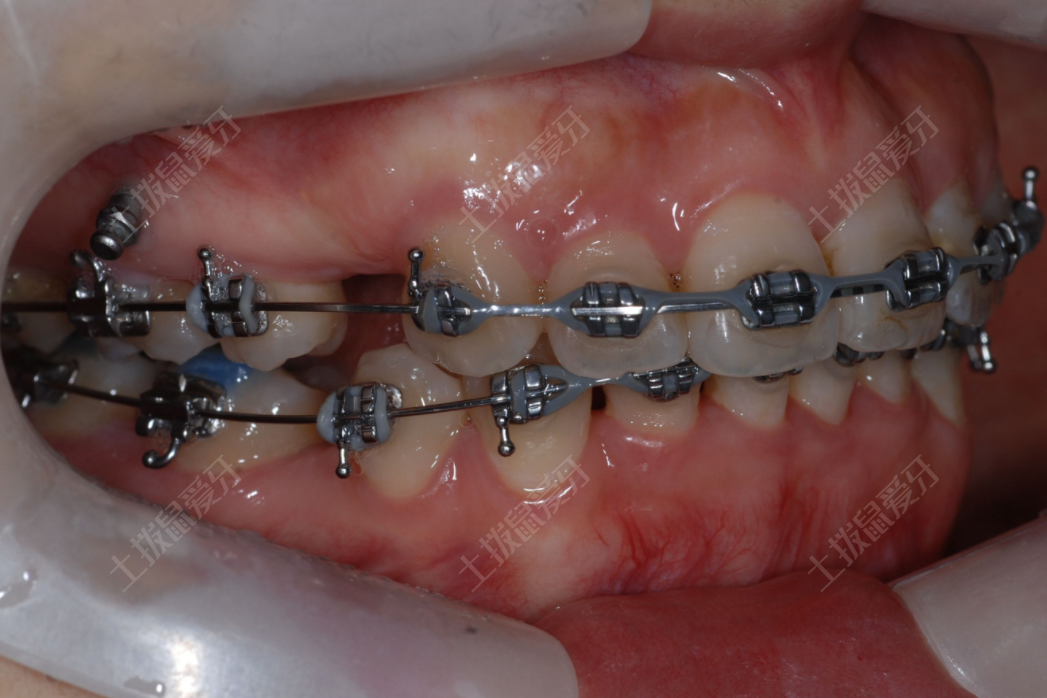

有不少小伙伴想做矯正,但遲遲不敢行動,就是因為聽到醫(yī)生建議要拔牙,而且還是牙拔4顆,他們特別擔心牙齒拔掉之后會有什么危害,而且為什么要拔4顆這么多?你是不是也是在擔心這個問題呢?今天小編就給你一一道來。

首先我們需要明白正畸拔牙的原因,多數情況下,是因牙列擁擠,牙槽骨容納不下那么大的牙量,而采取的一種為牙槽骨減負的措施。這時就需要通過拔牙為牙列提供足夠的間隙,使牙列擁擠的矯治獲得成功。

另一方面來說,如果牙列擁擠,往往因為不易清潔,而使相關牙易蛀壞或發(fā)生牙周炎,而縮短牙的使用壽命。而拔牙矯正后,牙齒排列整齊,易于清潔,除了改善美觀外,功能行使正常,能夠使牙的壽命延長。

所以答案是只要正確的拔牙,那么牙齒矯正過程中的拔牙就是有益無害的。

人類口內的恒牙一般數量為28-32顆,在拔牙案例當中,大部分案例會選擇拔除上下左右(四個象限)各1顆雙尖牙??谇粌让款w上排牙齒都有相互對應的下排牙齒,相互協(xié)作,完成咀嚼功能,保證牙弓及面部的對稱性及美觀性。如果單純拔除某一象限的牙齒,關閉間隙,會導致牙齒中線的不對正、牙弓的偏斜、咀嚼功能的異常、口周肌的異?;蛘呙娌康钠?。